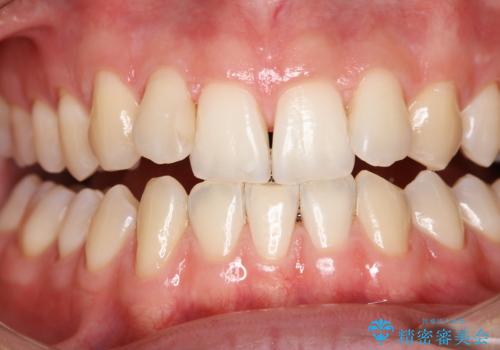

クリーニング(PMTC)掲載症例数554件

最新 クリーニング(PMTC)症例

ホワイトニング掲載症例数239件

最新 ホワイトニング症例